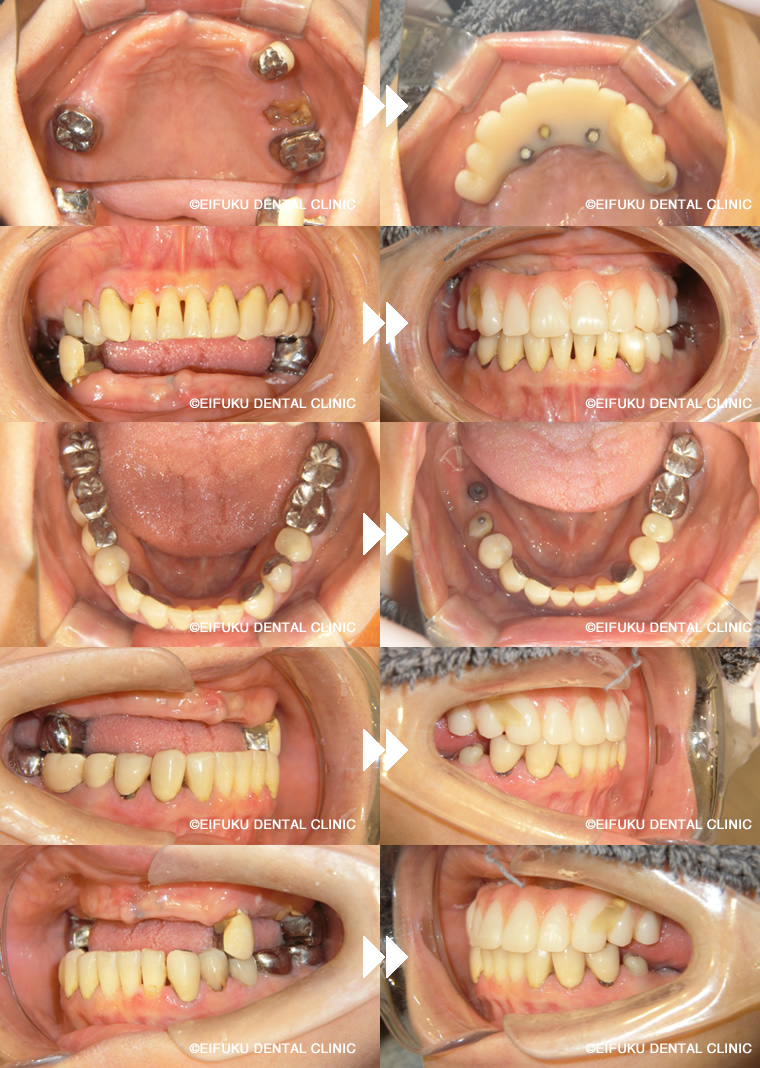

| コメント | 40代の男性、患者さんは、「歯が動いてしっかり噛めない」「歯ぐきから血が出る」「歯が割れてしまった」というお悩みで来院されました。 重度の歯周病と歯の破折が進行しており、上顎の多くの歯は保存が難しく、このままでは仕事や日常生活に支障が出るほど噛む力が低下している状態でした。「とにかく早く噛めるようになりたい」「総入れ歯にはしたくない」という患者さんのご希望から、上顎は左右の頬骨にインプラントを固定するザイゴマインプラントを用いたオールオン形式の治療計画を立案しました。 通常のオールオン4では骨量が不足しているケースでも、頬骨を利用することで強固な固定が得られ、ブリッジ状の固定式の歯を支えることが可能になります。精密検査のうえ、残存歯を抜歯しながら同時にザイゴマインプラントを埋入し、十分な初期固定を確認したうえで、その日のうちに固定式の仮歯を装着しました。術後まもなく柔らかい食事から再開でき、「ぐらぐらせずしっかり噛める」「人前で思い切り笑えるようになった」と大変喜んでいただけました。ザイゴマインプラントを用いたオールオン形式は、歯がボロボロで動いている、歯ぐきから血が出る、歯が割れて噛めないなど重度の症状でも、短期間でしっかり噛める状態を目指せる治療オプションです。 当院では、骨量不足や重度歯周病でお悩みの方に対しても、専門的なインプラント治療と丁寧なカウンセリングで、早期に「噛める」「見た目も回復する」ことを重視した治療をご提案しています。 |